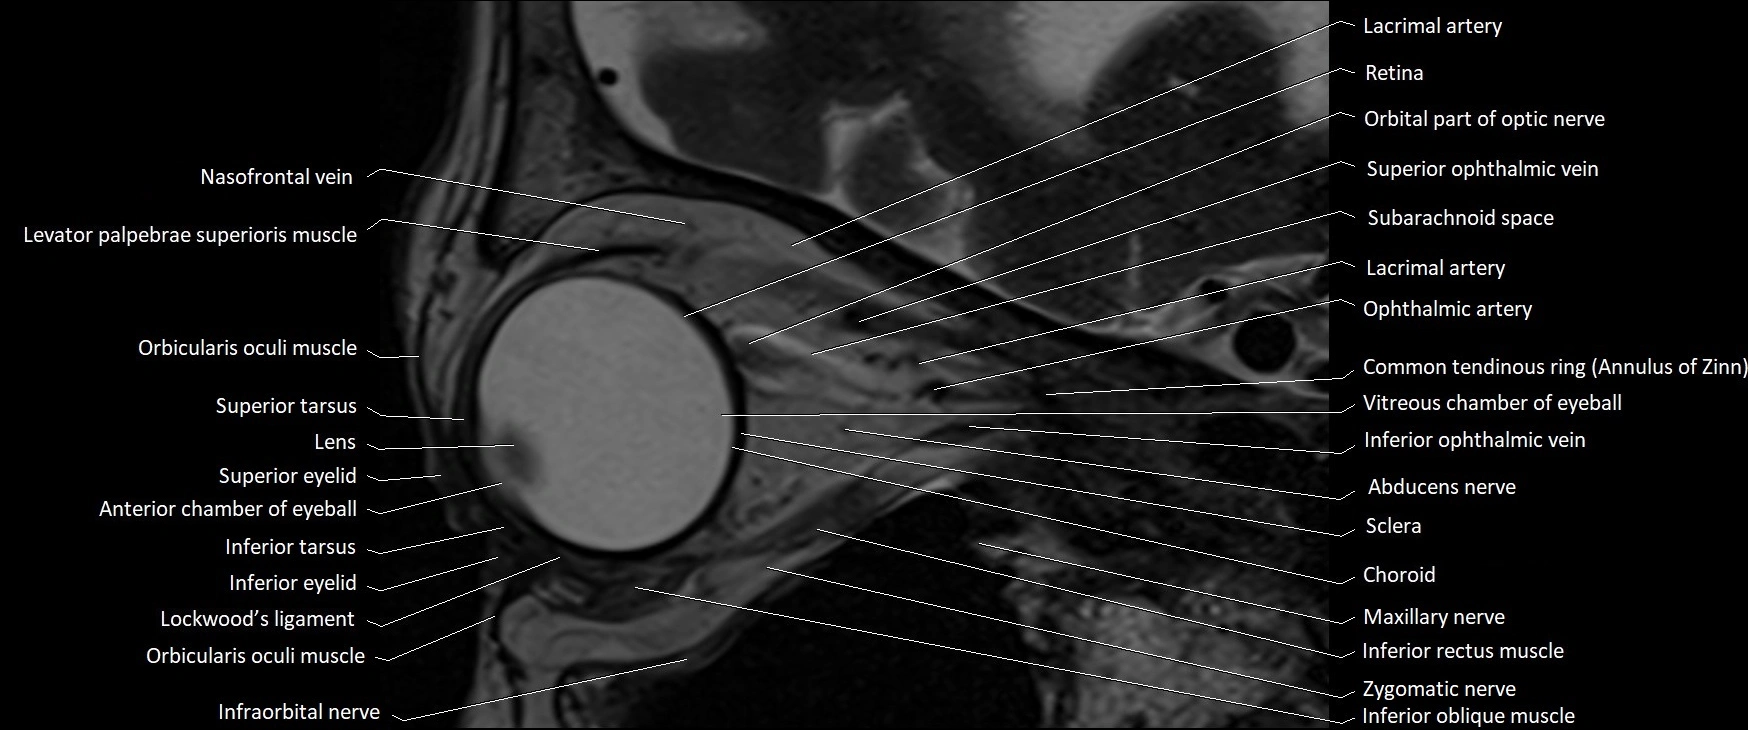

MRI images